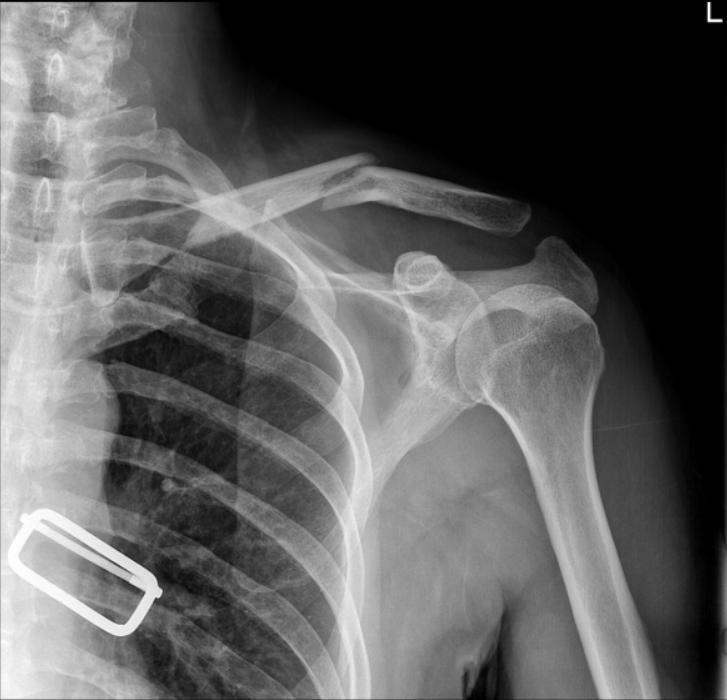

术后立即肩部x线片显示,锁骨骨折切开复位和Knowles针内固定后,肩锁关节(ACJ)明显移位。根据Rockwood分型诊断为V型ACJ脱位